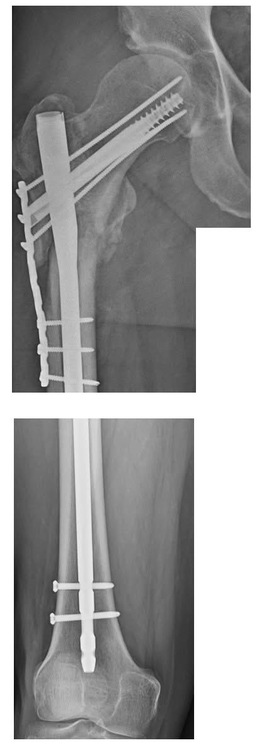

It’s been nearly six months since my broken femur. I’m healing up slowly. When I meet with my ortho surgeon next month I’ll know if things have healed up enough. I’m still weak and limp without a cane. That’s due to the weakened side glutes. Here is the before and after pics of the break. |